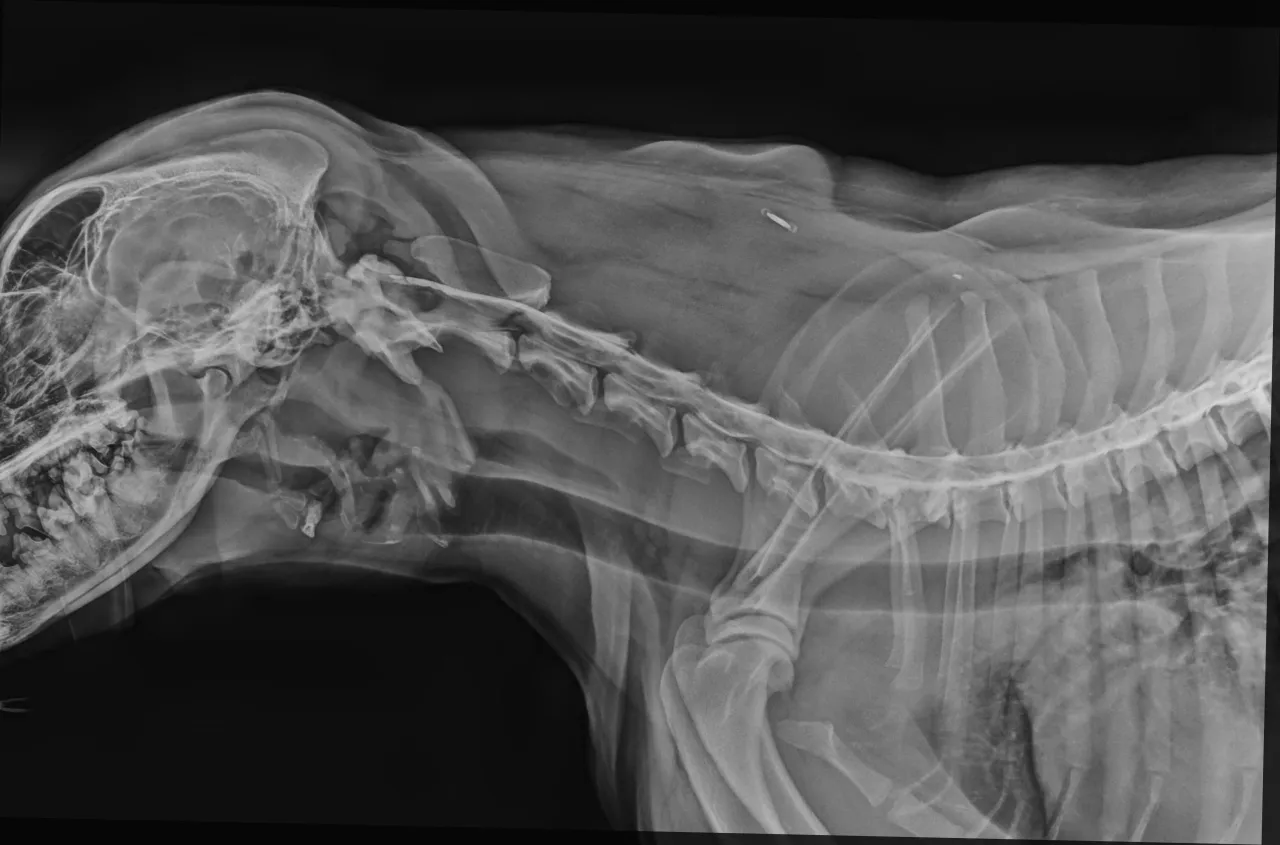

Chondrodystrofia to nie tylko kwestia wyglądu, ale przede wszystkim genetycznie uwarunkowane zaburzenie rozwoju chrząstek, które u jamników wpływa bezpośrednio na budowę dysków międzykręgowych. U większości psów dyski te zachowują elastyczność przez długie lata. U jamników jednak, ze względu na chondrodystrofię, jądro miażdżyste dysków (czyli ich miękki, galaretowaty środek) ulega przedwczesnemu zwyrodnieniu i zwapnieniu. Staje się twarde, kruche i traci swoje właściwości amortyzujące. W efekcie, zamiast pełnić rolę amortyzatora, taki dysk staje się podatny na wypadanie (ekstruzję) lub pękanie (protrusję) nawet przy pozornie niewielkim urazie czy nieprawidłowym ruchu. To sprawia, że jamniki są w grupie najwyższego ryzyka dyskopatii, a proces degeneracji może rozpocząć się już w bardzo młodym wieku.

- Typ I (Hansen I): Jest to najczęstszy typ u jamników i innych ras chondrodystroficznych. Polega na nagłym wypadnięciu (ekstruzji) zwapniałego jądra miażdżystego do kanału kręgowego. Powoduje to silny ucisk na rdzeń kręgowy, co objawia się nagłym bólem, niedowładem, a nawet paraliżem. Przebieg jest zazwyczaj ostry i bardzo dynamiczny.